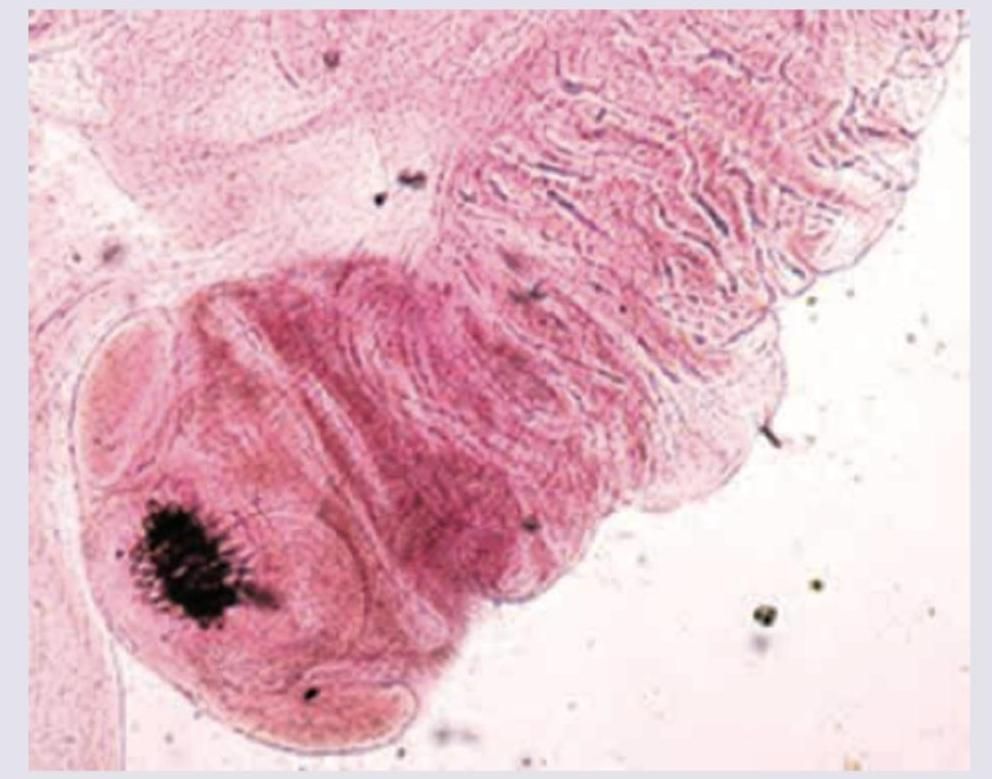

Which of the following is incorrect about the condition shown below?